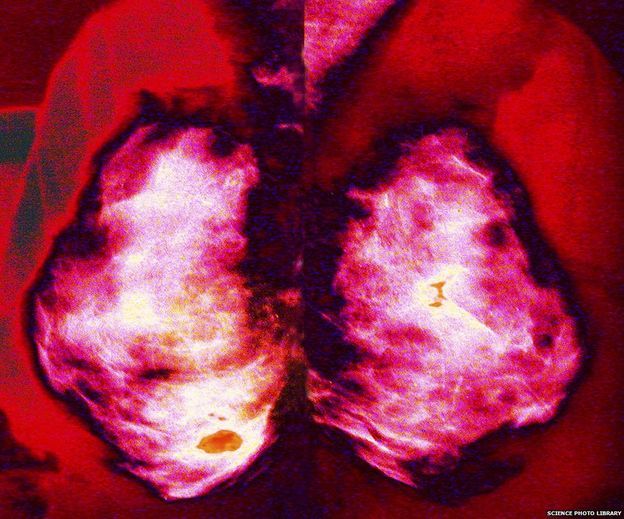

Una mamografía puede detectar un cáncer de mama pero hay muchos expertos que no la recomiendan.